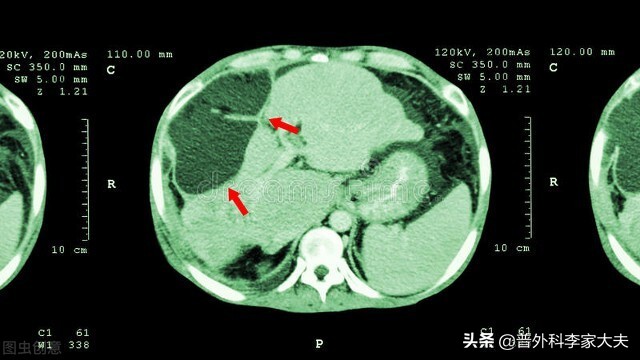

肝癌单纯介入治疗

肝癌

文献报道,晚期肝癌单纯介入治疗的中位生存期为12个月左右,显然疗效超过肝癌的免疫治疗,对有条件的患者与家庭来说,自然价值更大。但晚期肝癌介入治疗是有适应证要求,并且,晚期肝癌介入治疗的疗效好坏,与介入治疗的技术操作密切相关。如果介入医生能够做到真正超选择荷瘤血管支化疗栓塞治疗,自然疗效好、副作用少。但如果介入化疗栓塞不到位,不但疗效差,而且还有可能给患者带来严重的副作用,结果就是钱花了,人也不好了。因此,最终是否有价值,也要根据患者的自身情况与对家庭的影响来评判了。